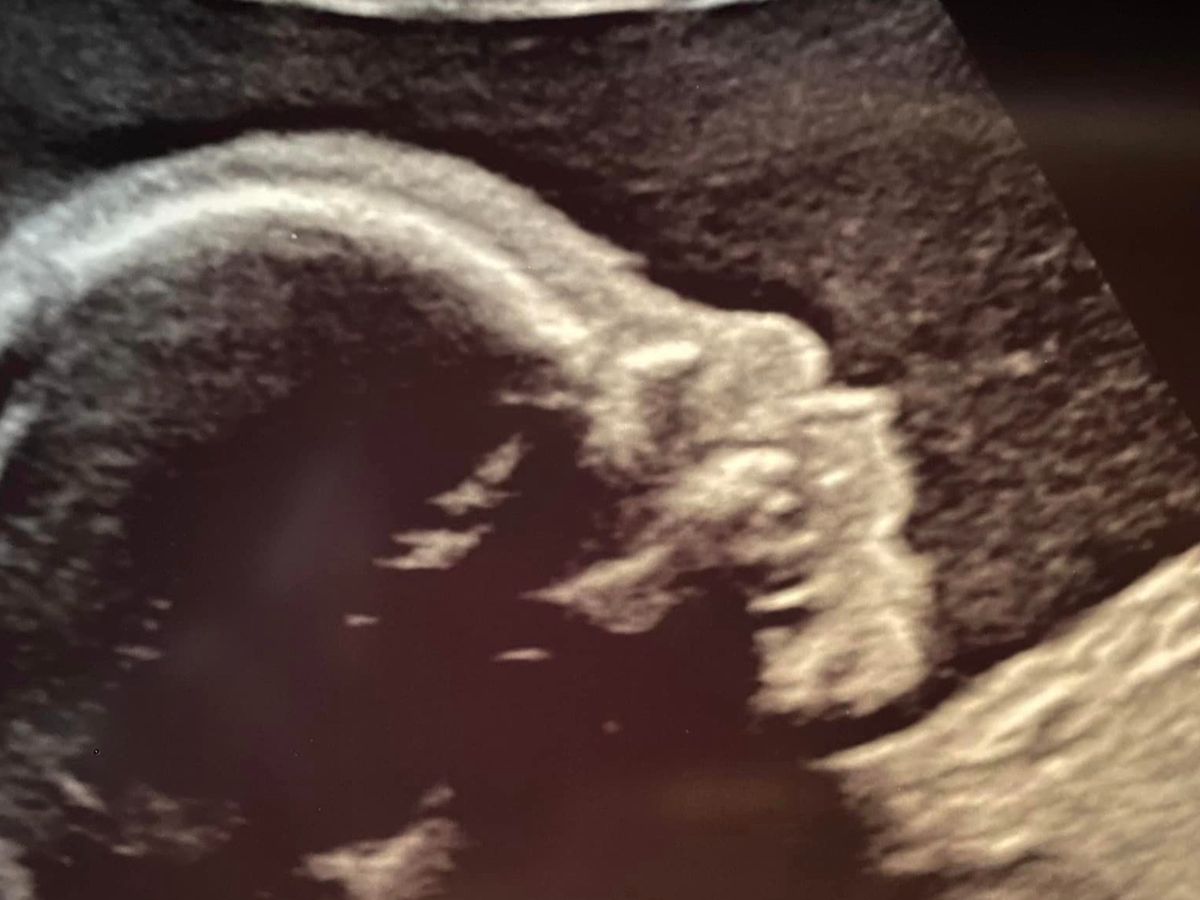

Baby Penny and her family

Hi everyone! My name is Shannon, and I am raising funds for a small family that needs a lot of help. Melissa and Corey have been through so much already. They have three beautiful, sweet little girls: Ali, Mia (4) and Claire (2).  The family faced the devastating news two years ago that Ali had cancer. Ali was a trooper, fought the battle and won. Fast forward to this year. Melissa and Corey are expecting a new bundle of joy, Penny. They recently discovered that Penny has an issue with her umbilical cord and her heart.  I will post more information in the paragraph below.  After already facing a battle with cancer, this new struggle will cause a financial strain. Let's face it; everything is a financial strain right now. Melissa's mom was a very dear friend of mine and, unfortunately, passed away when the twins were just one. Will you help me give this family a little financial relief and take some of the burden and stress off them, especially at Christmas?

Here is more information on Penny's struggle. The umbilical defect is called Absent Ductus Venosus or Ductus Venosus Agenesis. It is scarce, and there seems to be no cause; it is how she developed. The ductus venous regulates how much blood flow is sent directly into the heart. Penny’s is missing. That means that blood is being dumped into her heart at a much higher rate than it should be. Half of her heart is already slightly enlarged (much more, and her surgery will be more complicated), and it is overworking - it is like she is constantly running a marathon. This is the immediate concern as her chance of cardiac arrest in the womb is very high, but if her heart can tolerate it, it will mostly not be an issue once she is born, depending on how severe it gets before birth.

Her heart defect is called Complete Atrioventricular Canal Defect. This is where the middle wall of her heart never formed properly, causing oxygenated and non-oxygenated blood to mix and not transfer oxygen to her body as efficiently as it should. This heart defect will require open heart surgery when she is several months old, which is terrifying, but the surgery has a very low (5%) complication rate. This is yet another issue for which there is no known cause; it is simply how her heart formed.